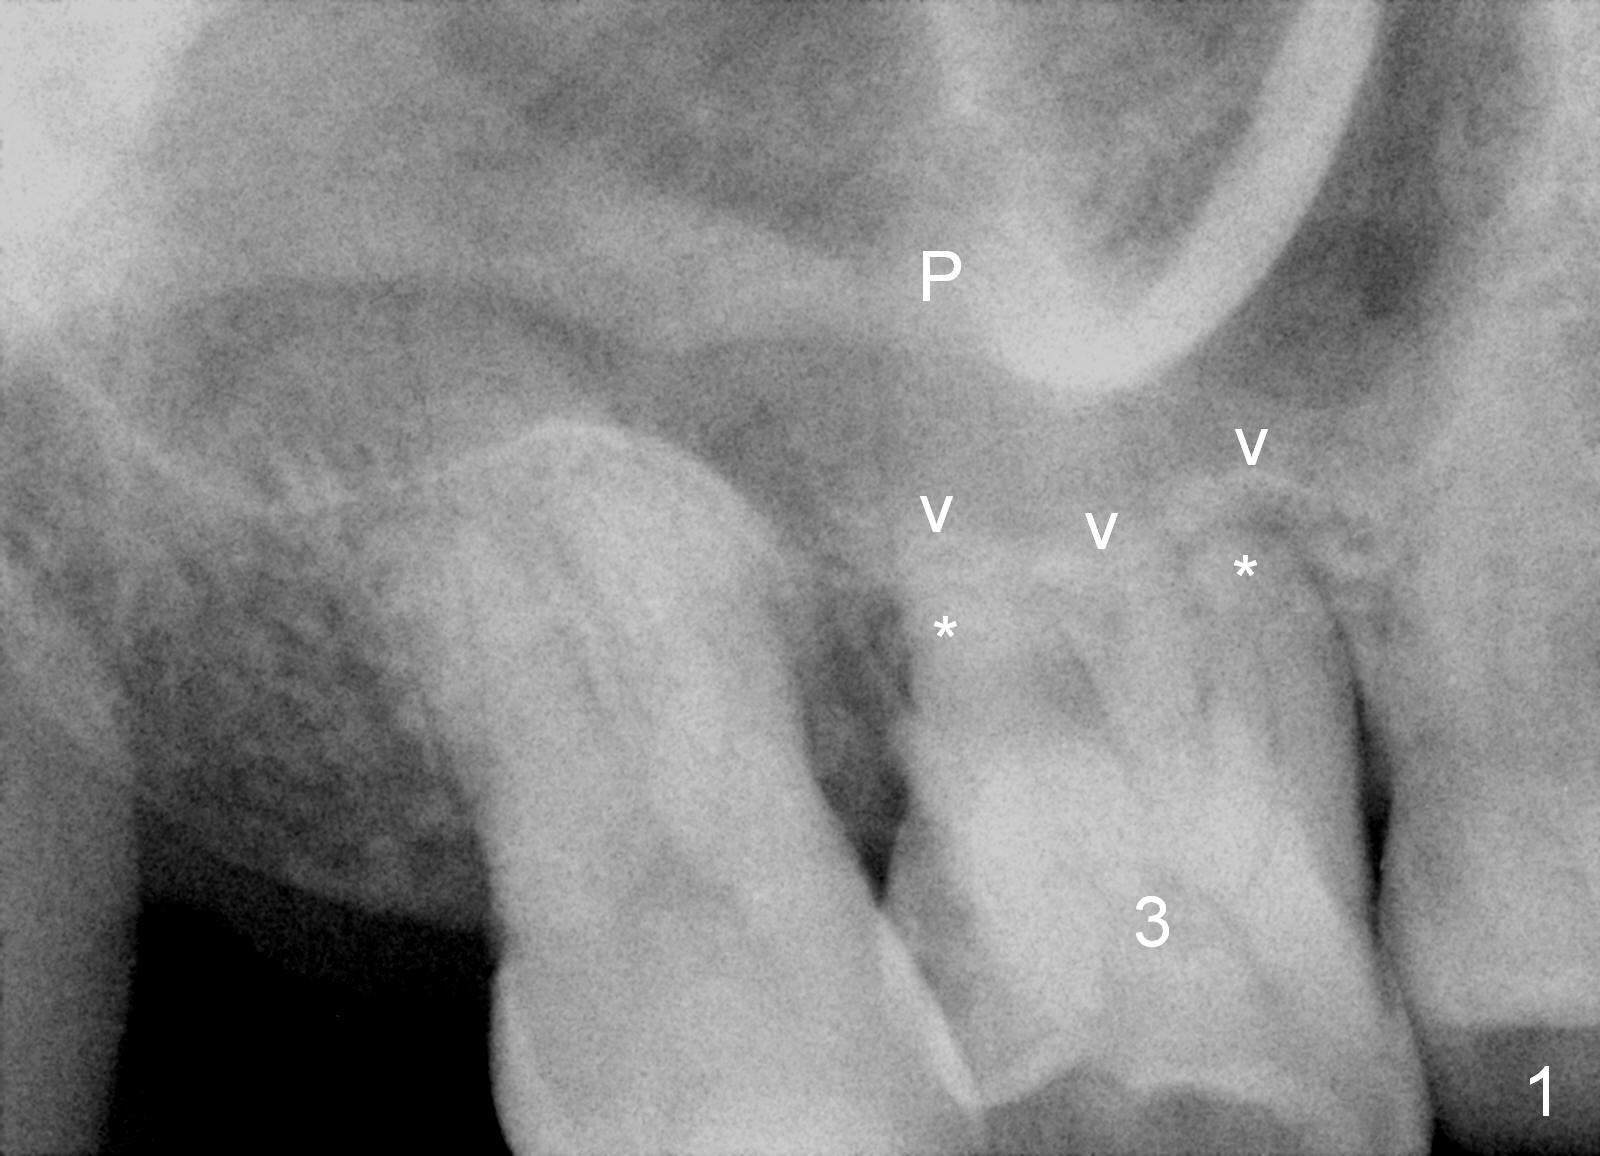

A 43-year-old man will return for #3 implant placement, 2.5 years after extraction. Pre-extraction PAs (Fig.1,2, taken 5 and 2.5 years ago) show that the palatal apex (Fig.1 P) is much higher than the buccal ones (*). The tooth became non-salvageable because of caries (Fig.2 C) in 2.5 years with periapical radiolucency (*). After extraction, the bone available for implantation is probably below the sinus floor (Fig.1,3 arrowheads), 7-9 mm.